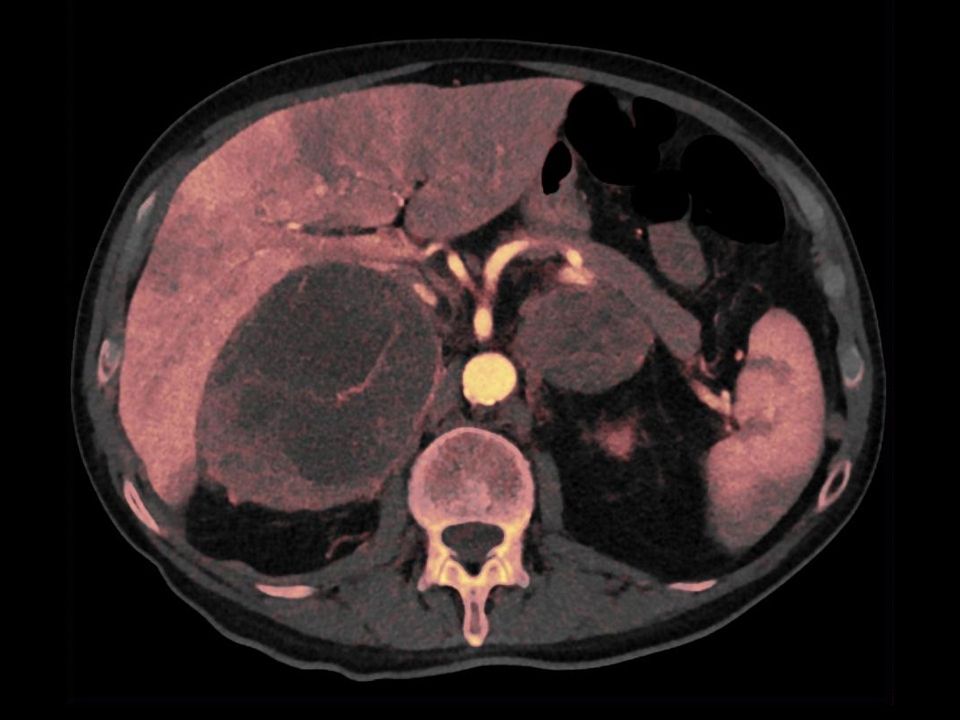

CT DE Virtual Unenhanced

Quantify lesions with two scans in one.